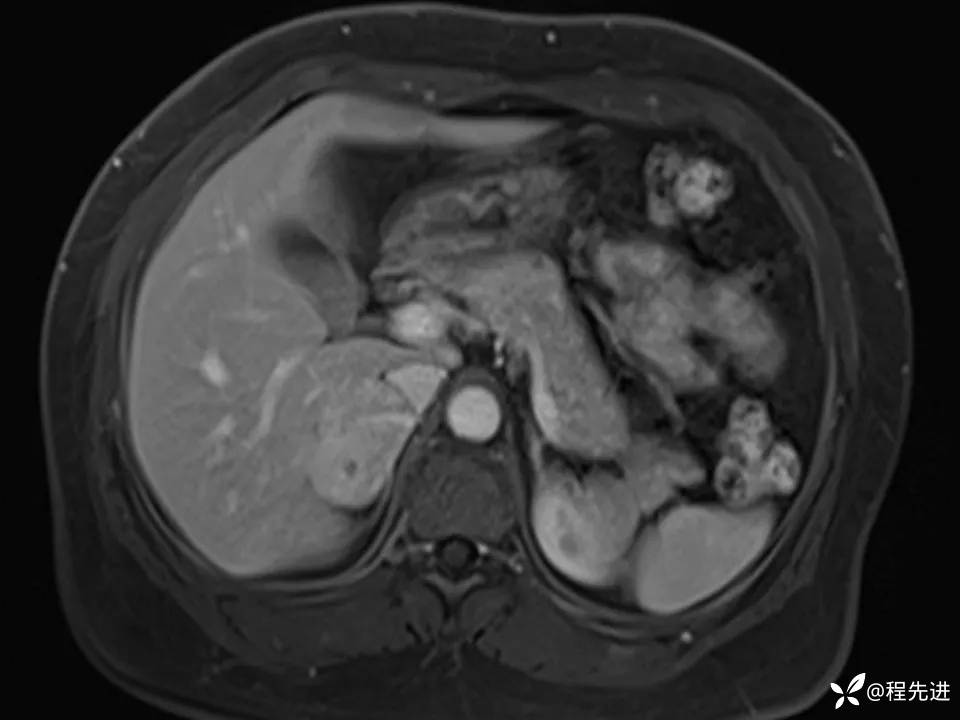

患者性别:女

患者年龄:44岁

简要病史:体检发现肝占位性病变2月余

既往:有高血压病史1月余,口服药物控制可

实验室检查阴性。